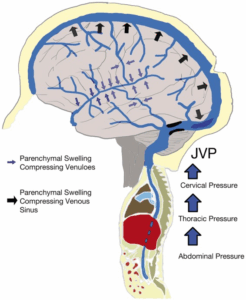

頭蓋内圧や脳圧の亢進、または頭蓋内高血圧の症状をお持ちの方が頻繁に来院されています。目の奥から頭痛が発生したり、心臓の鼓動に合わせて聞こえる拍動性耳鳴りがあったり、悪心、嘔吐、めまいを訴えられます。一晩中横になっている姿勢では脳浮腫がさらに悪化する可能性があるため、朝起きる時に頭痛があり、咳をする時や頭を下げる時のように頭蓋内圧を増加させる行為によって頭痛がさらに悪化するともおっしゃいます。また、首、肩、背中部位の痛みが多く、視神経浮腫による羞明や目のかすみといった眼症状を伴い、耳鳴り、ジストニア、斜頸、後頸部痛などの症状を訴えられます。